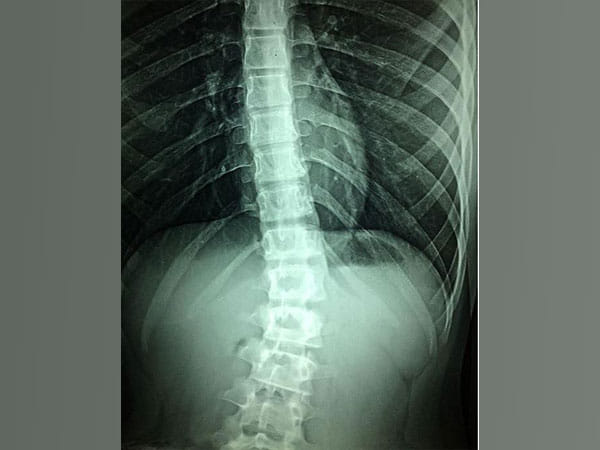

“Spinal Cord Injury remains one of the most debilitating traumatic injuries a person can sustain during their lifetime, affecting every aspect of the person’s life,” explained Professor Collins.

“The debilitating disorder results in paralysis below the level of injury and, in the US alone, the annual healthcare costs for SCI patient care are $9.7 billion. As there is currently no widely available treatment, continuous research into this field is crucial to find a treatment to improve the patient’s quality of life, with the research field turning towards tissue engineering for novel treatment strategies.